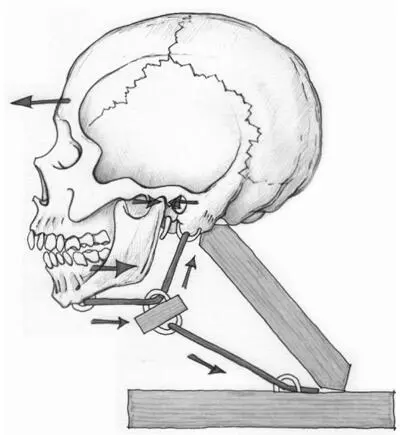

Abb. I.60: Verbindungen zwischen Unterkiefer, Kopfstellung und Halswirbelsäule

Auch die Stellung und Funktion des Unterkiefers und der Halswirbelsäule sind für den Ansatz von Wichtigkeit. Die Kiefergelenke bilden mit der Halswirbelsäule, dem Schädel und dem Schultergürtel eine Funktionseinheit. Im Gegensatz zum Oberkiefer ist der Unterkiefer kein Teil des Schädels, sondern frei beweglich und über Muskulatur mit dem Zungenbein – und damit auch mit der Zunge und dem Vokaltrakt – verbunden. Hierdurch wird der Unterkiefer bei möglichen Fehlhaltungen des Kopfes und der Halswirbelsäule direkt in Mitleidenschaft gezogen. Abb. I.60 illustriert, wie die Muskulatur unterhalb des Zungenbeins den Unterkiefer zurückhält, wenn der Kopf nach vorn bewegt wird. Dies führt zu einer erhöhten Kompression in den Kiefergelenken, welche wiederum Schmerzen und eine Beeinträchtigung des Spielgefühls nach sich ziehen kann (vgl. S. 37). Gerade Bläser sind jedoch auf ein freies und bewegliches Kiefergelenk für die Tonbildung angewiesen. Die Nähe der Kiefermuskulatur und die enge Verbindung der Halswirbelsäulenmuskulatur zum Ohr und seiner Blutversorgung können mögliche Erklärungen dafür liefern, warum bei einer starken Funktionsstörung des Kiefergelenks oder der Halswirbelsäule Ohrgeräusche auftreten können.